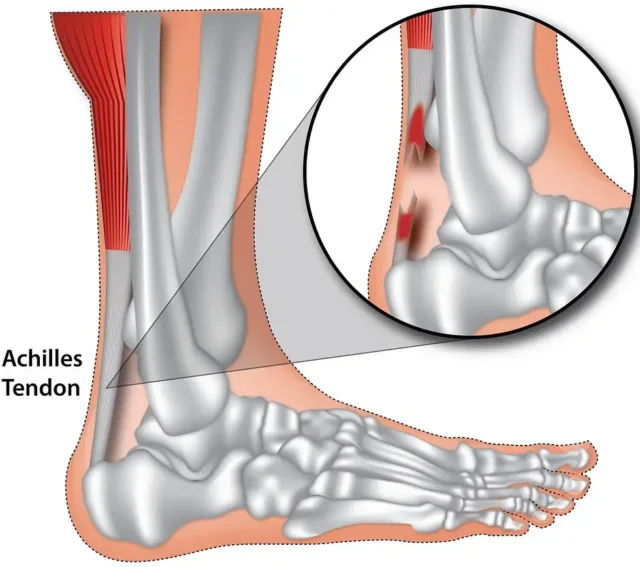

Stres kırığı, aslında tam olarak bir kırık değildir. Ayağın yük taşıması sırasında her bölgenin farklı işlevleri vardır. Yürüyüş esnasında ayağın her bölgesi belli miktarda yük taşır. Ancak ayağın anatomik yapısı zorlanırsa ve yanlış yerlere fazla miktarda yük bindirilirse kemiğin basınç altında kalmasına sebep olunur. Basınç ise tarak ve kaval kemiklerinde ödeme neden olur. Ödem geliştikçe kemiğin içerisindeki basıncı arttırır. Bu basınç ise hastaya ağrı olarak yansır.

Stres kırığı daha çok alt baldır kemikleri ve ayak tarak kemiklerinde meydana gelir. Bunun sonucunda ise küçük çatlaklar meydana gelir. Araştırmalar sonucu stres kırığının daha çok enerji gerektiren sporları yapan kişilerde oluştuğu görülmüştür. Bu enerji gerektiren sporlar ise basketbol, tenis, atletizm gibi sporlardır. Çünkü bu sporlarda zemine ayak çarpma hareketi daha çok yapılır. Stres kırığı ayrıca saha ve pist sporları ile uğraşanlarda da görülebilir.